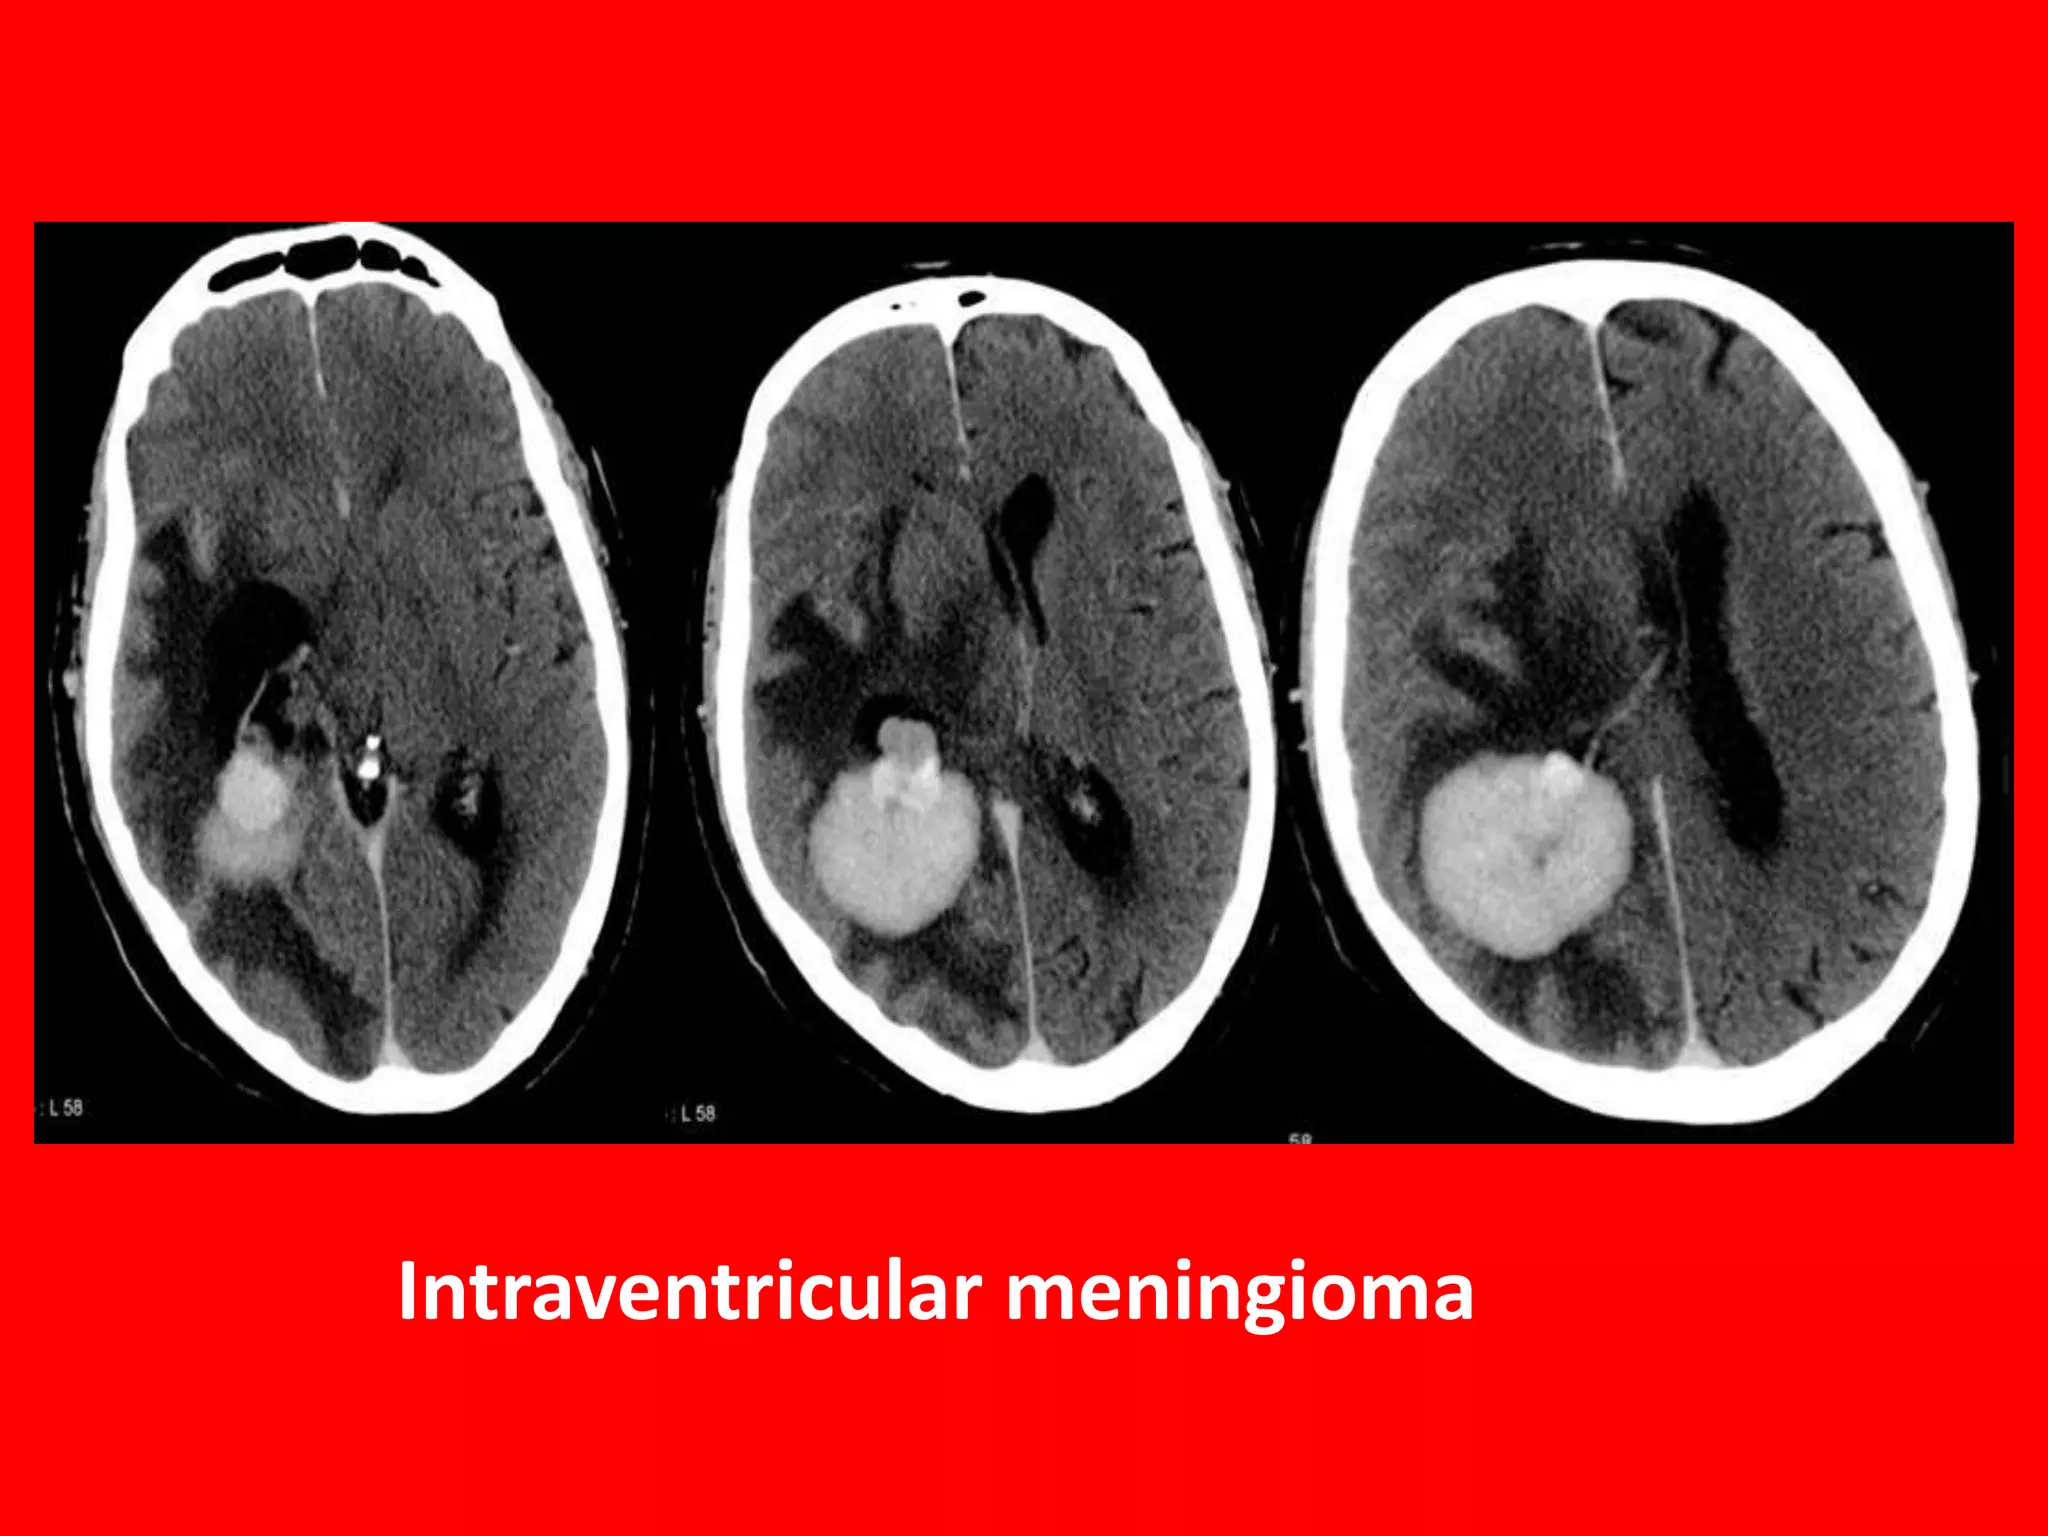

Intraventricular meningiomas are rare

intracranial tumours that represent an

uncommon subtype of the more-classical

extra-axial meningioma and represent

between 0.5 and 2% of all

meningiomas. Despite its rarity, they

represent one of the commonest adult

intraventricular neoplasms 4.

80% trigone of lateral ventricle

15% third ventricle

5% fourth ventricle

Intraventricular meningioma